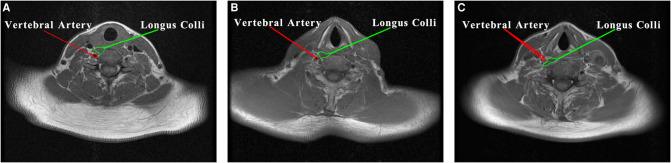

RESULTS

By the interventions on the 30 patients, the middle and posterior routes were shorter than the anterior route in length, but with no statistical difference between the two routes. Of 30 contralateral vertebral arteries, 26 were located at the posterior medial edge of the longus colli. The average included angles of the anterior, middle, and posterior routes were 108.02 ± 7.89°, 95.51 ± 6.52°, and 72.48 ± 4.65°, respectively. According to these data, the middle route was optimally applied to 50 patients, in whom the rate of nerve transplantation was only 4%, and no serious complications such as vertebral artery or brachial plexus injury occurred.

结果

对30例患者进行干预后,中路和后路的长度短于前路,但两者之间无统计学差异。30条对侧椎动脉中,26条位于颈长肌后内侧缘。前路、中路和后路的平均夹角分别为108.02±7.89°、95.51±6.52°和72.48±4.65°。根据这些数据,中路被最佳地应用于50例患者,其中神经移植率仅为4%,且未发生椎动脉或臂丛神经损伤等严重并发症。